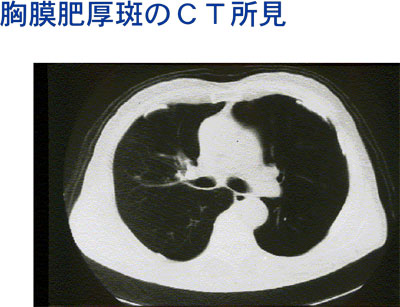

アスベストの健康障害は簡単に言うと、じん肺の一つのアスベスト肺、肺がん、悪性中皮腫(肺の外の膜にできるがんの一種は悪性胸膜中皮腫)の3種類があります。腹膜の回りにできる中皮腫は悪性腹膜中皮腫と言います。もう一つは、良性の変化ですが、胸膜肥厚班があります。(図2)

図2

これがCTでみた胸膜肥厚班です(写真11)。

写真11